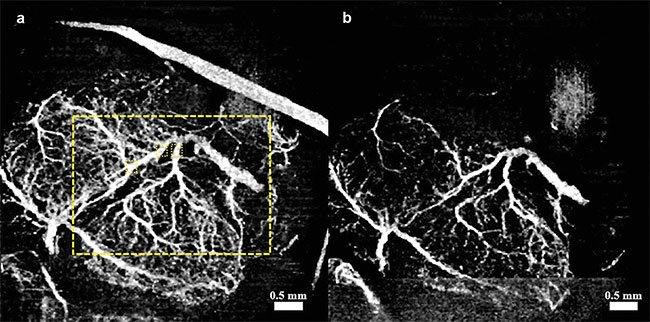

Figure 1. Vasculature changes in the embryonic brain before (a) and 45 min after (b) maternal exposure to ethanol. Adapted with permission from Reference 10.

In recent studies, angiographic OCT was used to image murine fetal brain vasculature in utero10-12. A series of experiments documented changes in murine fetal brain vasculature minutes after maternal exposure to various drugs. Embryos of pregnant mice at embryonic day 14.5 were imaged. This period corresponds to the end of the first trimester and beginning of the second trimester in human development. Initial OCT imaging was performed, and the mother was administered the drug for the corresponding study. Subsequent measurements were taken of the embryo for a period of 45 min, at 5-min intervals.

For the experiments that tested the effects of alcohol, 16.6% ethanol at a dose of 3 g/kg was used. This dose was based on gas chromatographic analysis of mice with blood alcohol concentrations that were similar to those observed in humans who engage in risky patterns of drinking, such as binge drinking, but do not yet have an alcohol use disorder or addiction13.

Speckle variance OCT (svOCT) and correlation mapping optical coherence angiography (cmOCA) are two types of angiographic OCT techniques that were used in the studies. While svOCT calculates the variance between multiple images taken at the same spatial location, cmOCA calculates the correlation coefficient between the images to capture any dynamic scatterers (such as blood in this case) in the specific location. These procedures are followed at multiple consecutive locations to obtain a vasculature map. Once the 3D vasculature maps were obtained, the maximum intensity projections (MIPs) were calculated to obtain 2D images.

Figures 1-3 show the vasculature in the fetal brain before and after maternal exposure to ethanol, nicotine, and SCBs, respectively.

In all three cases, when compared to placebo groups, a drastic reduction in vessel diameter was observed within 45 min of maternal exposure, demonstrating the possibility that all three teratogens act as a vasoconstrictor on the fetal brain. Such constriction could have a drastic effect on normal brain development.